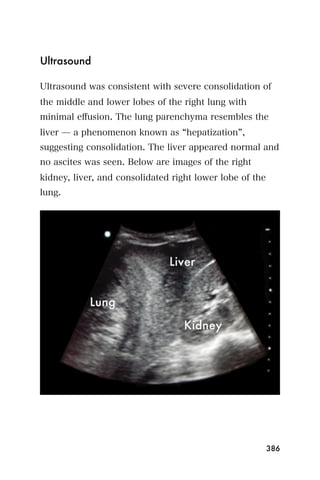

Color Doppler can also be used to evaluate the mitral

valve. Press the Color button and place the box over the

mitral valve and the entire left atrium. Blood going

toward the probe (towards the top of the screen) will

appear red, and blood going away from the probe will

appear blue. In Figure 13, mitral regurgitation appears

as a blue area starting at the mitral valve and going into

the left atrium during ventricular systole.

Figure 13. Apical four chamber view of a rheumatic mitral valve

showing regurgitation by color flow Doppler

This means that during systole, when the left ventricle is

contracting, there is blood leaking from the left ventricle

through the mitral valve into the left atrium. This mitral

regurgitation is abnormal.